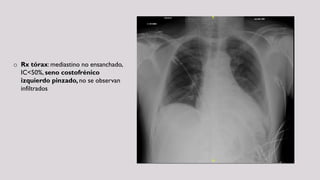

o Rx tórax: mediastino no ensanchado,

IC<50%, seno costofrénico

izquierdo pinzado, no se observan

infiltrados